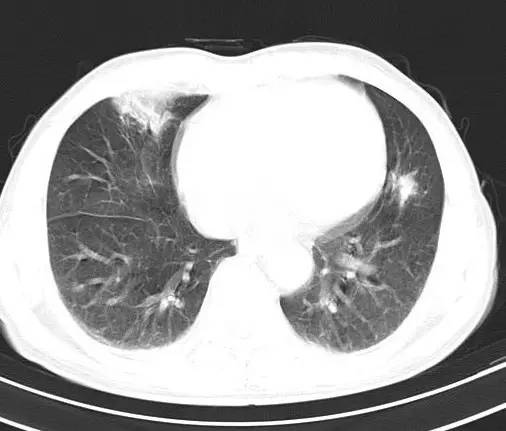

治疗后十天CT(图9-12):双肺病灶明显缩小,有所吸收。

金黄色葡萄球菌肺炎,抗炎治疗23天后完全吸收。